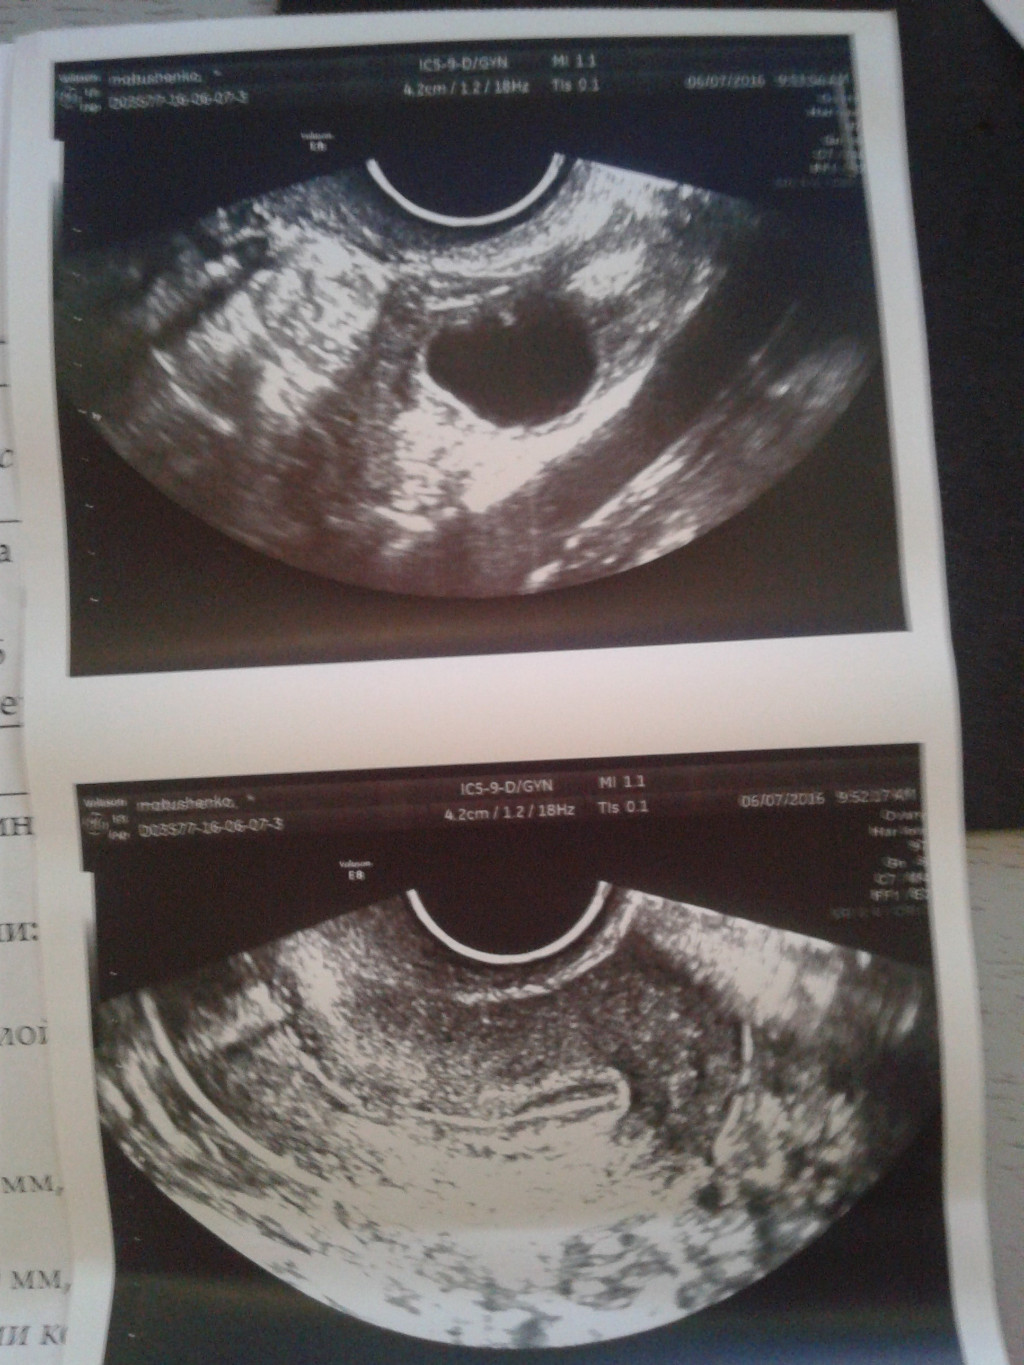

Трансвагинальное УЗИ

Специалист проведет этот тест в середине вашего цикла, до того, как обычно происходит овуляция.Этот визуализирующий тест используется для подтверждения наличия доминантного фолликула (кисты яичника с яйцеклеткой внутри). Используя это изображение, ваш врач также может измерить толщину и рисунок слизистой оболочки матки в это время.

Что такое тест подсчета антральных фолликулов?

Анализ антральных фолликулов — это трансвагинальное ультразвуковое исследование, при котором измеряется количество имеющихся у вас антральных фолликулов.Ультразвуковой техник или врач использует зонд, вставленный во влагалище, для исследования и подсчета количества антральных фолликулов в яичниках. Это занимает всего несколько минут, подобно гинекологическому осмотру.

Антральные фолликулы очень маленькие — от 2 до 9 миллиметров в диаметре — но их все же можно увидеть на УЗИ.

Количество видимых антральных фолликулов может дать вашему врачу примерное представление о том, сколько всего яйцеклеток (включая множество фолликулов, которые еще слишком малы, чтобы их можно было увидеть) осталось в ваших яичниках.